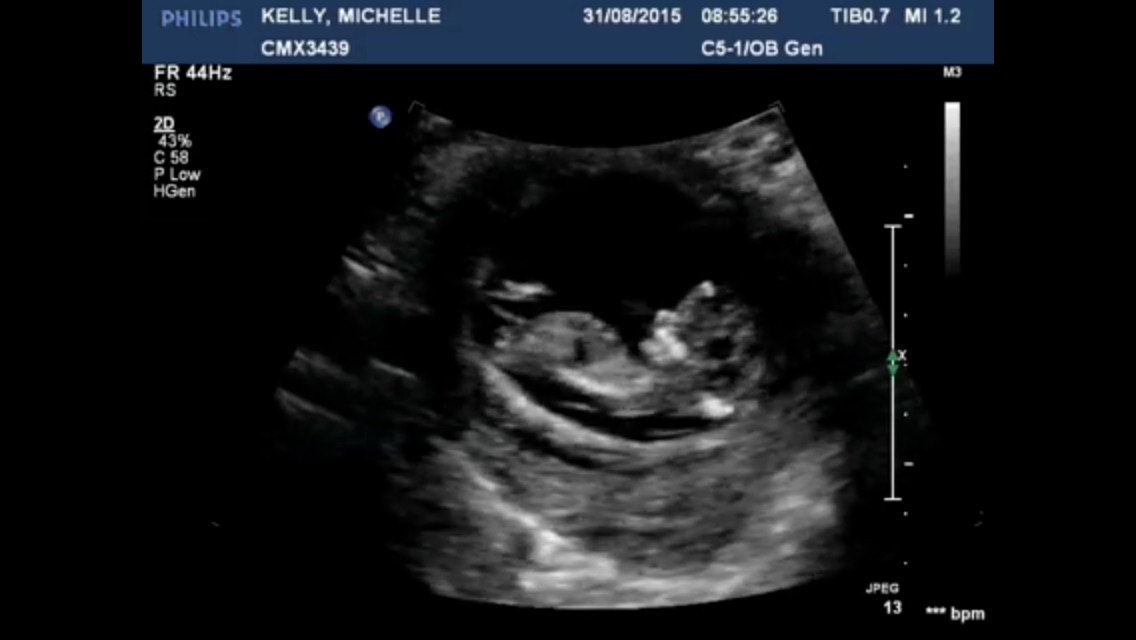

My first time visiting here id love you guys to take a guess if possible? I'm not even sure if the nub is visible, there is so much going on!

Both its huge lol

I think that's cord in the second. I'm not sure about the first either. Could be cord again as it's is super pointy and big for only 12 weeks 1 day.